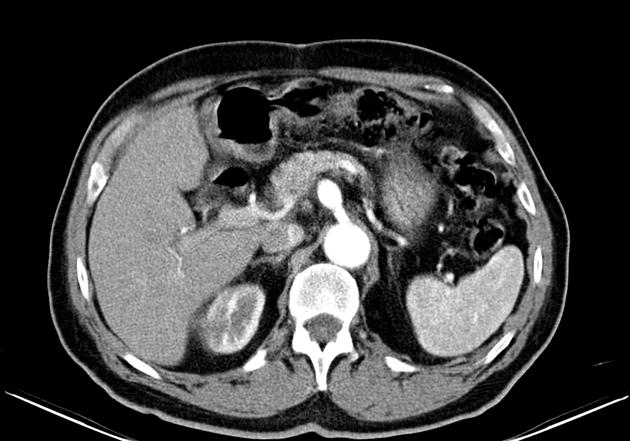

At the core of this discussion is a poignant case report detailing the treatment of a patient with a ruptured celiac artery aneurysm. Despite representing one of the rarer types of visceral artery aneurysms, the risk of rupture—ranging between 10% and 20% in the literature—is a scary reminder of the many twisted issues that surgeons need to resolve in high-pressure situations.

A celiac artery aneurysm involves a localized ballooning or bulging in the wall of the celiac artery, a key blood vessel supplying oxygenated blood to the upper abdominal organs. Patients may remain asymptomatic for long periods, with diagnosis often occurring when the aneurysm has already ruptured. Given the subtle symptoms and the hidden complexities of the condition, early detection remains a significant challenge.

Scientific observations have identified that although CAAs are the fourth most common among visceral artery aneurysms, the risk of rupture is not negligible. With rupture figures reported between 10% and 20%, the complications are intimidating due to their potential for massive internal bleeding and subsequent multiple organ failure. This underscores the pressing need for both early diagnosis and effective treatment strategies.

Minimally invasive techniques have fundamentally shifted the approach to vascular surgery, with endovascular procedures taking center stage. The case report in question details the successful use of an endovascular stent graft to treat a ruptured CAA, reflecting a growing trend towards procedures that reduce recovery times and complications.